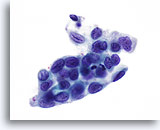

Adenocarcinoma in situ

Nucleoli can be indistinct to prominent. In this image, the nucleoli are prominent and present in a majority of the nuclei. Rapid fixation makes the presence of nucleoli another important piece of criteria in the diagnosis of AIS.

Biopsy – AIS – 60x